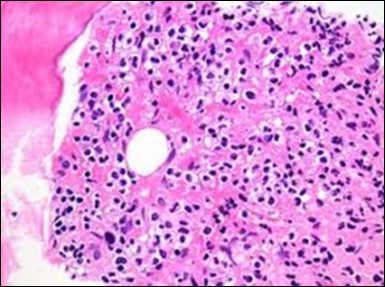

Figure 3.HCL: hairy cells dispersed within the native architecture(19).

HCL: hairy cells dispersed within the native architecture(19).